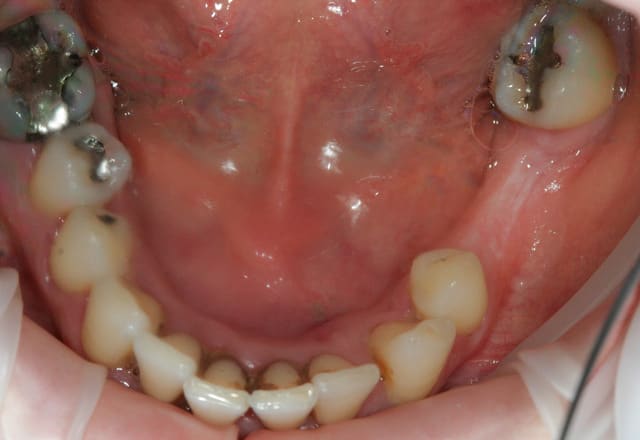

Paro ultra agressive chez une jeune femme de 30 ans.

Dans toute cette période, je n'ai pour ainsi dire quasiment jamais eu de cas de parodontite agressive aussi importante que celle ci.

la patiente est très jolie, elle a 30 ans, a consulté deux ou trois dentiste en l'espace de 10 ans, le dernier détartrage date il y a trois ans et il n'a pas été terminée apparemment car la patiente avait trop de douleurs, et aujourd'hui elle est adressée par un hôpital parisien qui devait lui poser des implants et qui devant la panoramique a renoncé sans pour autant la diriger correctement.

Principalement les lésions en forme de cuvettes que l'on retrouve en secteur 2 et 4. Cette forme de lésions permet une meilleure tenue du biomatériau et permet un afflux sanguin perpendiculairement à la paroi. C'est le même principe que la cicatrisation d'une alvéole intacte sans paroi manquante.

Théoriquement après cica, on peux esperer une réossification au mieux jusqu'à la limite haute de la cuvette.

...il y a autre chose: trés peu de dents postérieures soutiennent l'occlusion, et on est en début d'effondrement, avec les antérieures qui commencent à partir en éventail.

Paradoxalement c'est une bonne nouvelle: aprés l'assainissement général, la pose d'implants servant de butées peut améliorer considérablement la suite dans ce genre de cas.